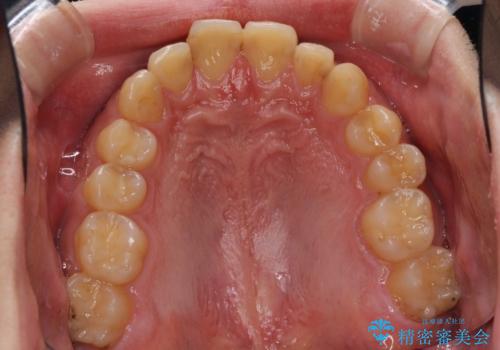

- 上下前歯のデコボコと下の前歯が隠れるほどの深い咬み合わせを気にして来院された患者様です。

インビザラインによる上下歯列の拡大と、IPR(歯と歯の間を削る)にるスペースの獲得により、口元のデコボコとディープバイトを改善することとしました。

デコボコがなくなったことで日頃の清掃が行いやすくなり、深い咬み合わせが改善したことで、食いしばりによる顎の負担も軽減されました。